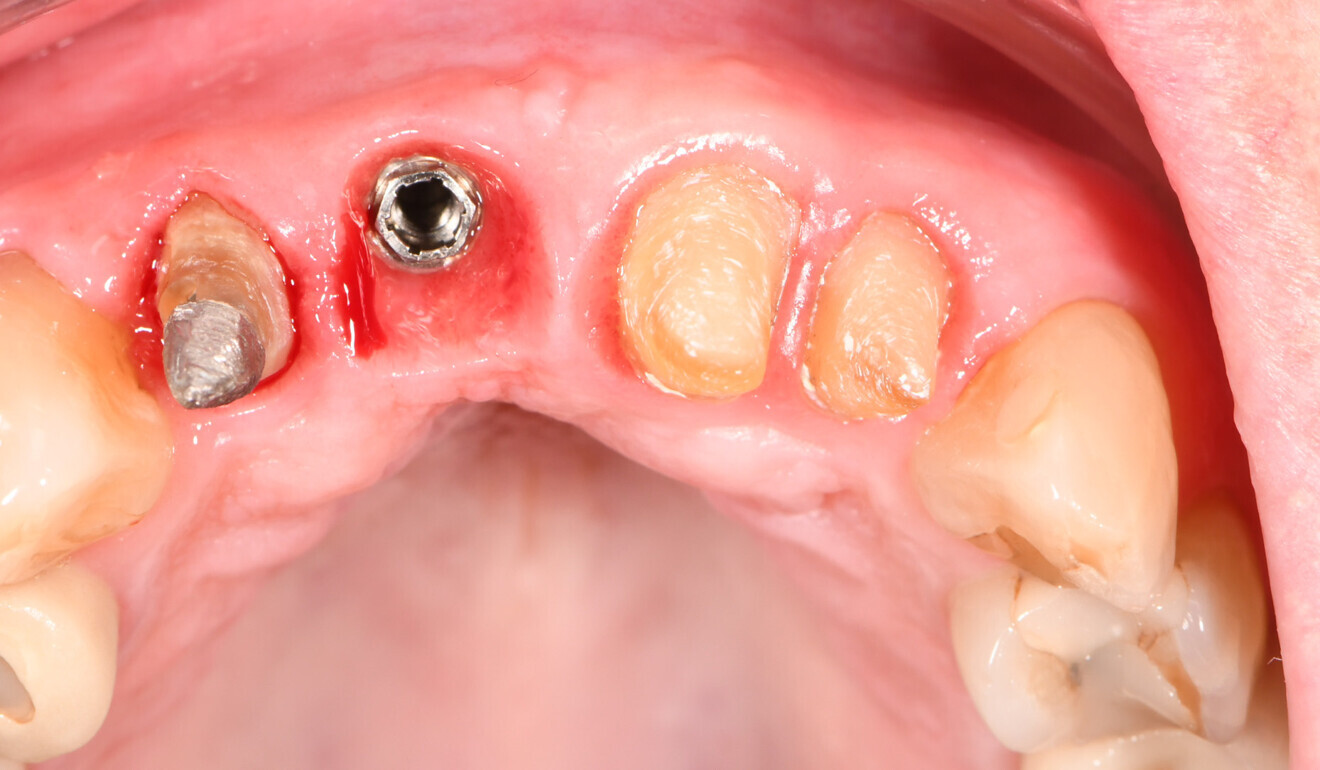

Fig. 12: Intra-oral situation prior to restoration placement.

Based on the data set of the temporary restorations, four separate crowns—one for the implant and three for the teeth—were designed in full contour. Without any anatomical reduction, the restorations were milled from KATANA Zirconia YML. Based on the evaluation of the temporary restorations, the shade selected this time was Shade A3.5. CERABIEN ZR FC Paste Stain (Kuraray Noritake Dental) was used for external staining and glazing of the surface. The laboratory also cemented the implant-based crown to the gold-shaded titanium abutment (Elos Medtech) with PANAVIA V5 (Kuraray Noritake Dental) in the shade Opaque for an improved masking effect (Fig. 11). In the office, the abutment–crown was screwed on to the implant and the screw access hole closed with composite, and the three tooth-based crowns were then placed using PANAVIA SA Cement Universal (Figs. 12–15).